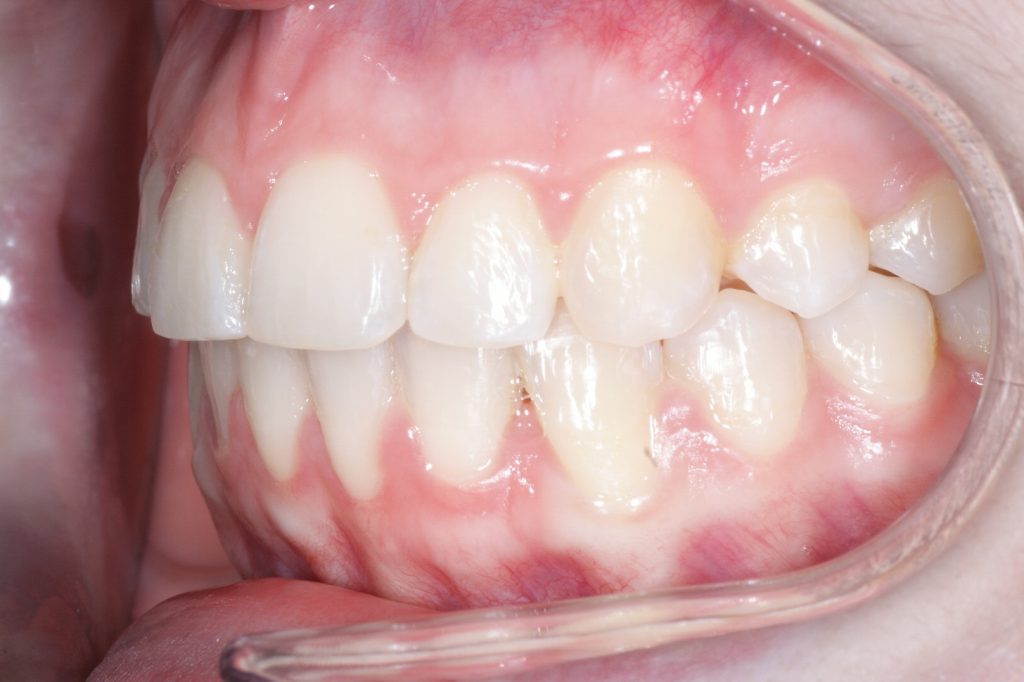

Correction d’une malocclusion de type Classe II division 1, surplomb horizontal inadéquat et chevauchement modéré aux 2 arcades. Des appareils fixes (broches et vis d’expansion) et des élastiques furent nécessaires pour améliorer ce sourire. Traitement chez une adolescente, réalisé en 18 mois.